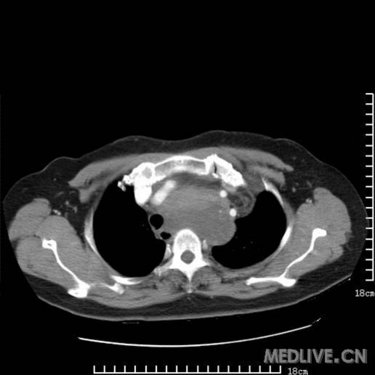

是胸腺瘤?畸胎瘤?高手支招_影像医学和核医学